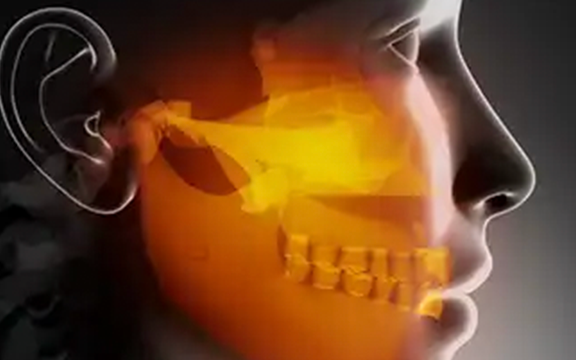

Temporomandibular Eklem (TME), alt çene kemiğini kafatasına bağlayan aynı zamanda, kayan bir menteşe gibi hareket eden bir eklem türüdür. Çenelerimizin her iki tarafında sağ ve sol tarafda birer adet olmak üzere iki adet çene eklemimiz bulunmaktadır.

TME bozuklukları ( hastalıkları ) çene ekleminde ve çene hareketini kontrol eden çiğneme kaslarında ( m. masseter ve m.temporalis ) ağrıya neden olabilir.

TME hastalıklarının belirtileri genellik ile şunlardır:

- Çenede var olan ağrı veya hassasiyet

- Temporomandibular eklemlerde ağrı veya hassasiyet

- Kulak içinde varolan ağrı

- Çiğnemede zorluk veya ağrı

- Yüz ağrısı

- Eklemde kilitlenme, ağız kapatma veya açmada zorluk